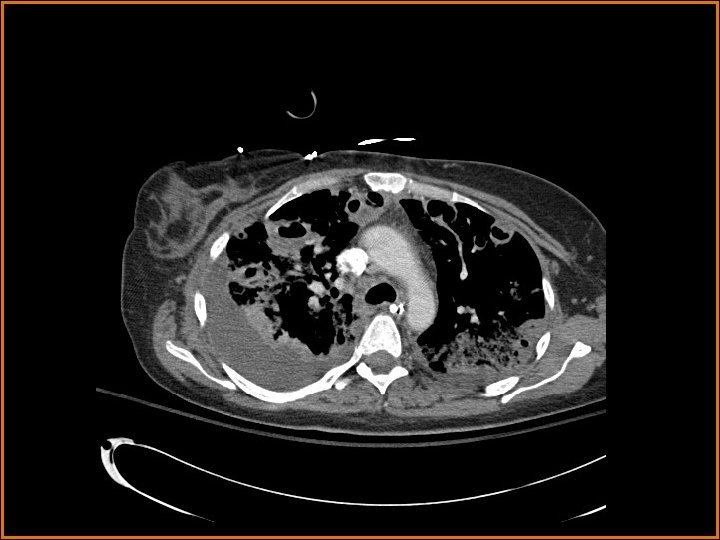

Findings and Differentials CT Findings: Multiple bilateral peripheral nodular opacities are seen, many of which are fed by arterial branches. Some of the nodules are cavitary. Diffuse bilateral ground glass opacities are seen with air bronchograms. The large lucency projecting over the right hemidiaphragm on the plain film corresponds to a pleural air collection that is directly contiguous with one of the cavities. Differential Diagnosis: • Multiple cavitary metastases • Septic Emboli

Discussion The differential diagnosis of cavitary nodules includes cavitary metastases, septic emboli, fungal infections, rheumatoid nodules, Wegener's granulomatosis, and rheumatoid nodules, among others. In this patient with fever, an infectious or inflammatory etiology is at the top of the differential. Correlation of the history with the imaging findings supports the diagnosis of septic emboli. Septic emboli usually manifest as multiple, bilateral peripheral opacities which may or may not cavitate. Often, the emboli will be in different stages of cavitation. Demonstration of a feeding vessel into the nodules indicates the hematogenous etiology of this process (although hematogenous metastases and a small-vessel vasculitis could certainly exhibit this feature also). Septic emboli may lead to pulmonary infarctions, which are seen as wedge-shaped opacities abutting the pleural surface, with the apex of the triangle pointing away from the pleura. The periphery of the infarct can enhance, but the center usually does not. Distinguishing infarcts from pneumonia is made easier when a vessel can be seen terminating at the apex of the infarcted region. (CONTINUED ON NEXT SLIDE)

Discussion (Continued) In this patient, the large right anteroinferior pleural air collection is contiguous with one of the cavities (as seen on the second CT image) and represents a bronchopleural fistula. Etiologies of bronchopleural fistulas include necrotizing infection, active TB, irradiation, tumor in a bronchial margin, etc. If the bronchopleural fistula is large, a persistent pneumothorax with or without contralateral mediastinal shift may be present. In this case, a septic embolus had eroded into the pleural space, creating the lucent collection projecting over the right hemithorax on the plain films. Finally, the ground glass opacities represented pneumonia in this patient.